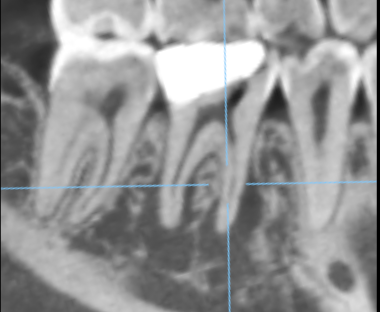

右下奥歯に瘻孔を認め、歯肉の腫脹を認めた。レントゲンで周囲骨が高度に吸収していた。

治療前